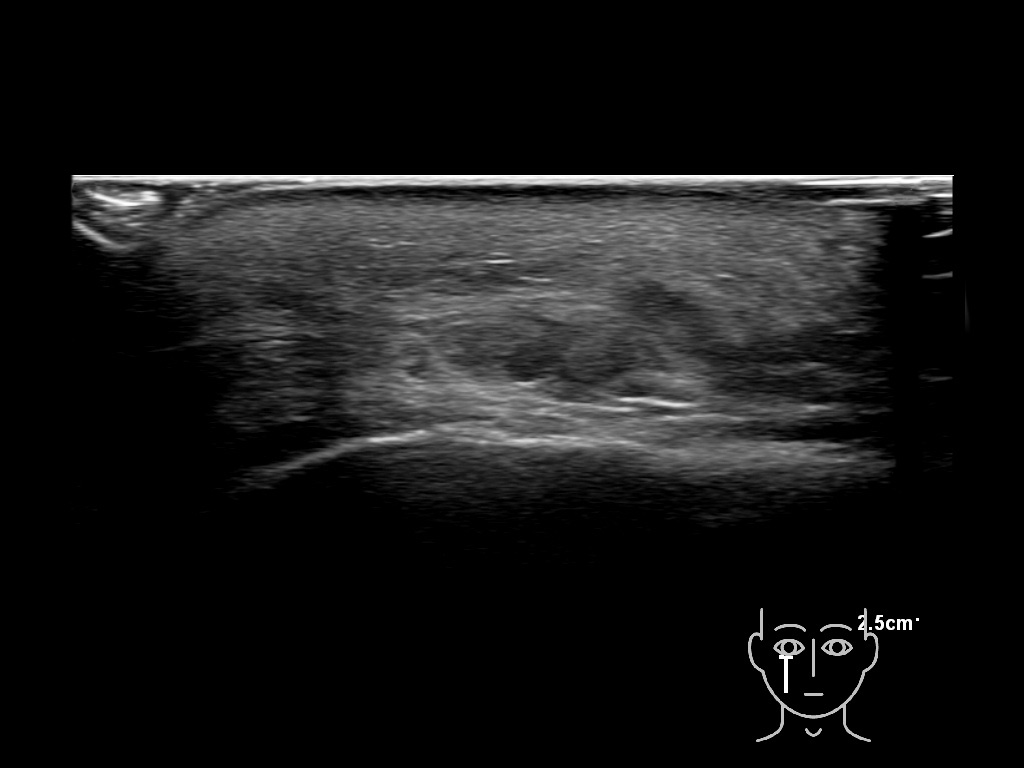

With ultrasound signs of inflammation can be visualized. Edema can be seen as a hyperechoic appearance of the subcutaneous fat, sometimes separated by hypoechoic fluid filled area’s, known as cobblestone appearance. Increased vascularization (hypervascularity) can be seen on colour Doppler. An abscess will appear as a fluid collection appearing as an irregular hypoechoic area with heterogeneous internal echoes and a thickened wall. Posterior acoustic enhancement can be present, and there is vascularity around but not within the mass. Under ultrasound guidance, abscesses can be managed by needle aspirations (18G) under antibiotic cover.

Study the first image to recognize the different layers. If you are sure about the layers, swipe to the second image to view the answer (if applicable).